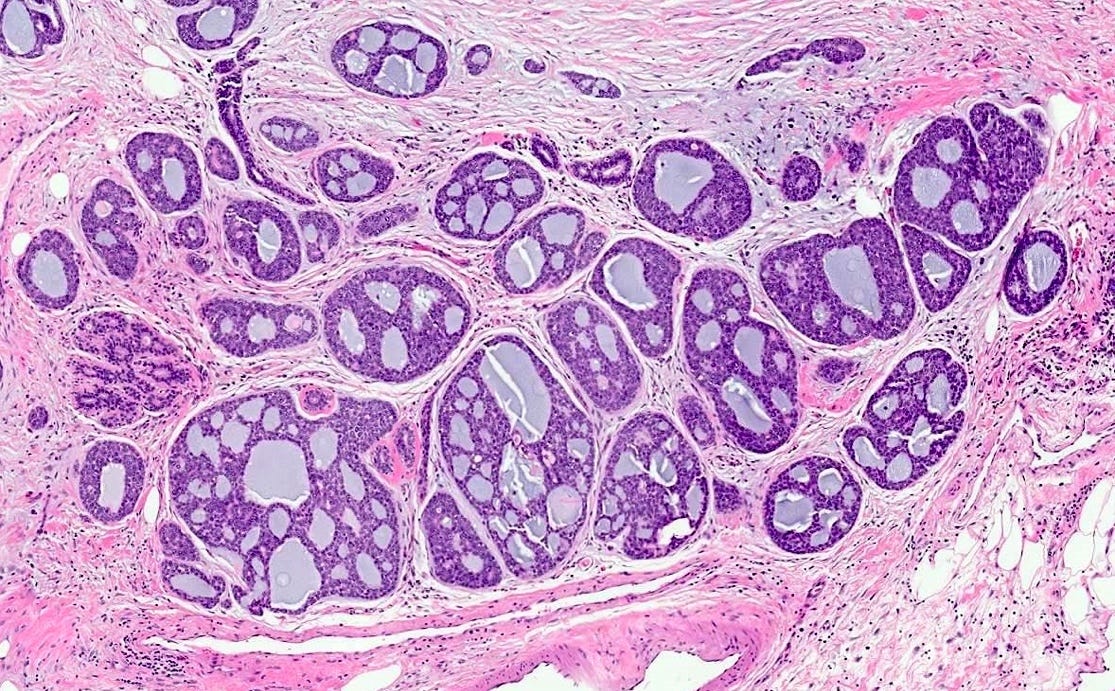

Polymorphic carcinoma - microscopic images

Note: due to its rarity in the breast, these images are from the similar tumor in the salivary glands

In reported cases, the tumor appears as a well circumscribed, firm mass. Microscopically, reported cases exhibited a wide spectrum of growth patterns, including solid nests, trabeculae, tubules, cribriform structures, strands and fascicles. In these cases, the tumor cells were monotonous with uniform nuclei and scant cytoplasm, lacking significant pleomorphism or mitotic activity.